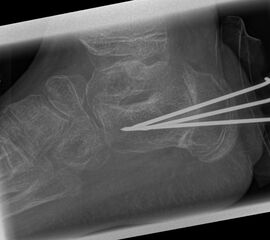

Abb.1 a-b: Beispiel einer noch offenen Wachstumsfuge im dorsalen Bereich des Calcaneus: (a) Alter 6 und (b) Alter 9 Jahre.

In der Regel bestehen aktive Wachstumsfugen bei Mädchen bis zum 12. und bei Jungen bis zum 14. Lebensjahr, mit Abweichungen von einem Jahr nach unten und nach oben. Präzise Informationen unter anderem darüber gibt das präoperative Röntgenbild (Abb. 2).

Abb. 2 a-c: offene Wachstumsfugen MT I Basis und Zehen (a), teilweise geöffnete Wachstumsfugen (b) und geschlossene Wachstumsfugen (c).